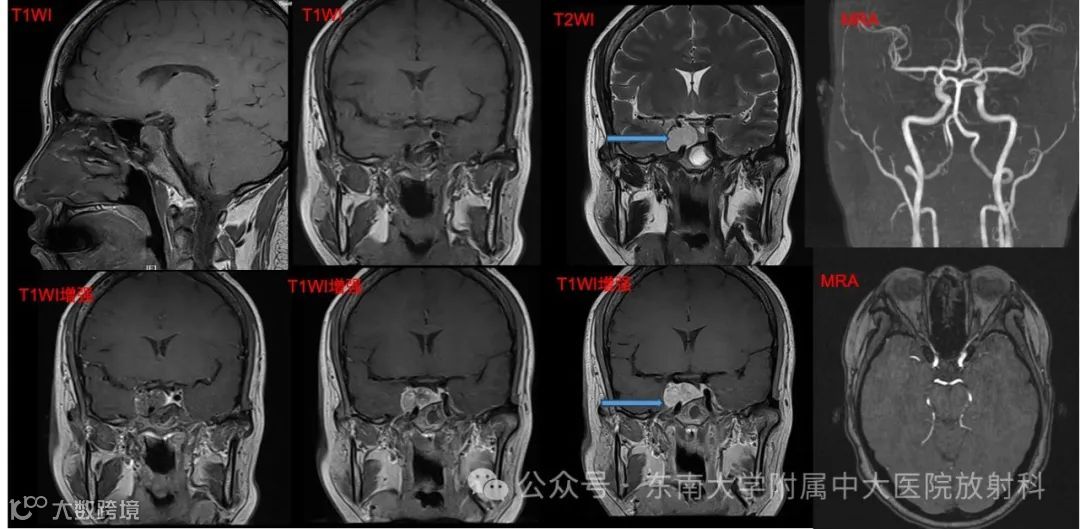

女,42岁 主诉:检查发现鞍区占位4天

现病史:患者4天前因“多关节疼痛”至我院风湿科就诊,考虑纤维肌痛,排查颅脑 MR 时发现鞍区占位。患者自觉鼻根至前额发胀,偶有头晕,按感冒及鼻炎处理无明显效果。无发热寒战,无视力障碍,无言语功能障碍,无心慌胸闷,无腹痛腹胀。现患者为求进一步诊治至我院就诊,病程中,患者神志清,精神可,饮食可,睡眠一般,二便正常,近期体重无明显下降。实验室检查无特殊

影像学表现